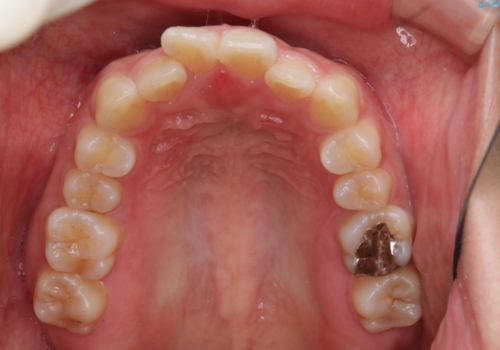

- 前歯のがたつきが気になるとご相談にいらした方です。当初は前歯の部分矯正をご希望されていましたが、全体的に整えることで審美的、機能的な歯並びとなりました。

当初は上顎前歯のみの部分矯正をご希望されていましたが、部分的に前歯のみを並べると出っ歯感がつよくなり、食事もしづらくなる可能性をお伝えしました。全顎的な矯正治療により、審美的、機能的な歯並びとなりました。